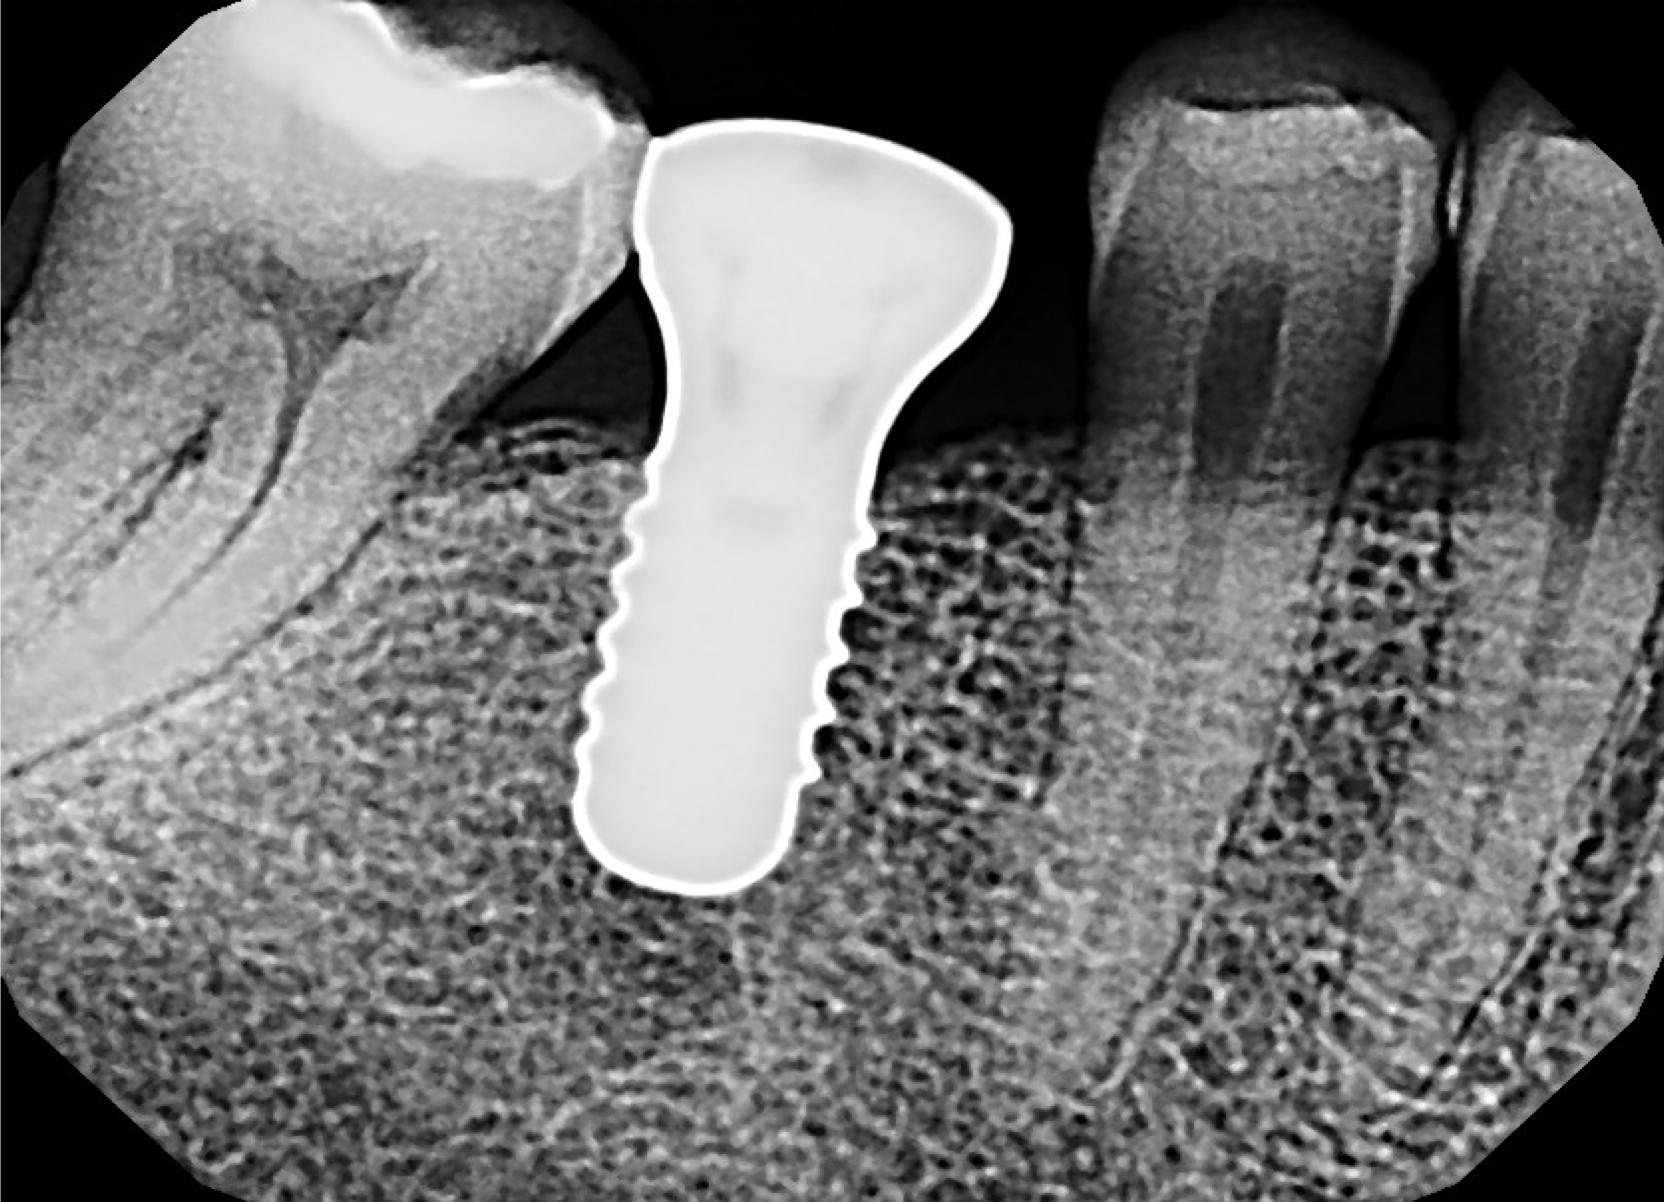

Gathering diagnostic data is the next step in properly assessing the patient. All types of diagnostics are not appropriate for every circumstance. For example, a periapical radiograph will not be the final stopping point for an implant placement, but it is a useful tool because it shows both bone quality and quantity. It can also demonstrate interradicular distance and contradicting pathology, which is useful for measuring the interproximal contact of the bone crest in various implant positions. However, as shown in Figure 6, it is not beneficial for every indication, especially on a cuspid where the implant is going to be placed in the corner of the mouth. It is virtually impossible to get a periapical radiograph repeatedly and predictably that will provide the appropriate distances needed.

Figure 6 showed a case where the patient presented with some internal resorption on tooth No. 11 that had been occurring for a number of years. The patient knew he needed an implant, but he also needed much additional work. The radiograph showed that the patient had internal resorption that could have started as external resorption but breached the tooth. There was also an infection in the alveolus that needed to be addressed with detailed planning.

Fig 6. A periapical radiograph can be useful for such factors as demonstrating interradicular distance and contradicting pathology, but it is not always beneficial, such as in the case of this cuspid for implant placement.

Figure 6